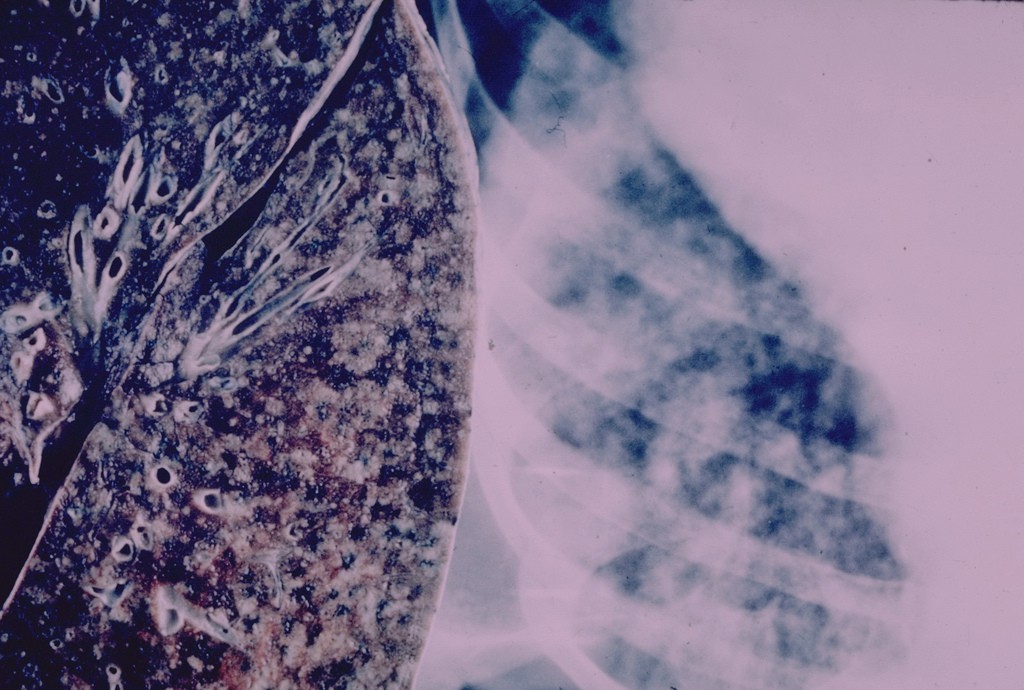

Przewlekła obturacyjna choroba płuc jest jednym z najczęściej występujących schorzeń dróg oddechowych. Mimo to wciąż niewiele osób potrafi rozszyfrować skrót POChP, oznaczający chorobę będącą połączeniem rozedmy płuc i przewlekłego zapalenia oskrzeli, prowadzącą nieuchronnie do systematycznego zmniejszania się pojemności płuc.

(BL/ Foto: Flickr.com/ Pulmonary Pathology)